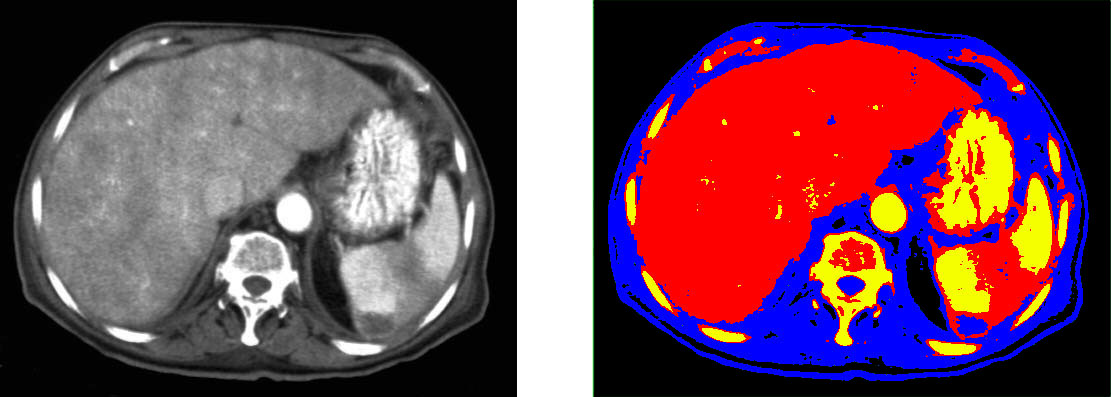

Segmentation of images is the process of partitioning the image into semantically meaningful parts and classifying each part into pre-determined classes. An example is depicted in Figure 1.2. As segmentation of medical images is a time consuming manual process, involving machine learning into this use-case has gained a high interest in the last years.

We have experimented with different values for the parameter: seemed to be too small as it could not separate a minimum of the required relevant features in the image, while starting with , the result image started to be too fragmented feature-wise. The 2D result for is presented in Figure 3.1. We also tried this algorithm in 3D on a CT volume for , as shown in Figure 3.2.

As it can be seen in the Figures 3.1 and 3.2, because the algorithm uses the pixels’ or voxel’s luminance levels to decide to which class each pixel belongs, and because multiple anatomical structures can have similar HU levels, this algorithm can not be used as such for the task of liver segmentation without any human intervention.

A sample segmentation result is presented in Figure 3.10, where, for reasons of space, we cropped the image around the liver.